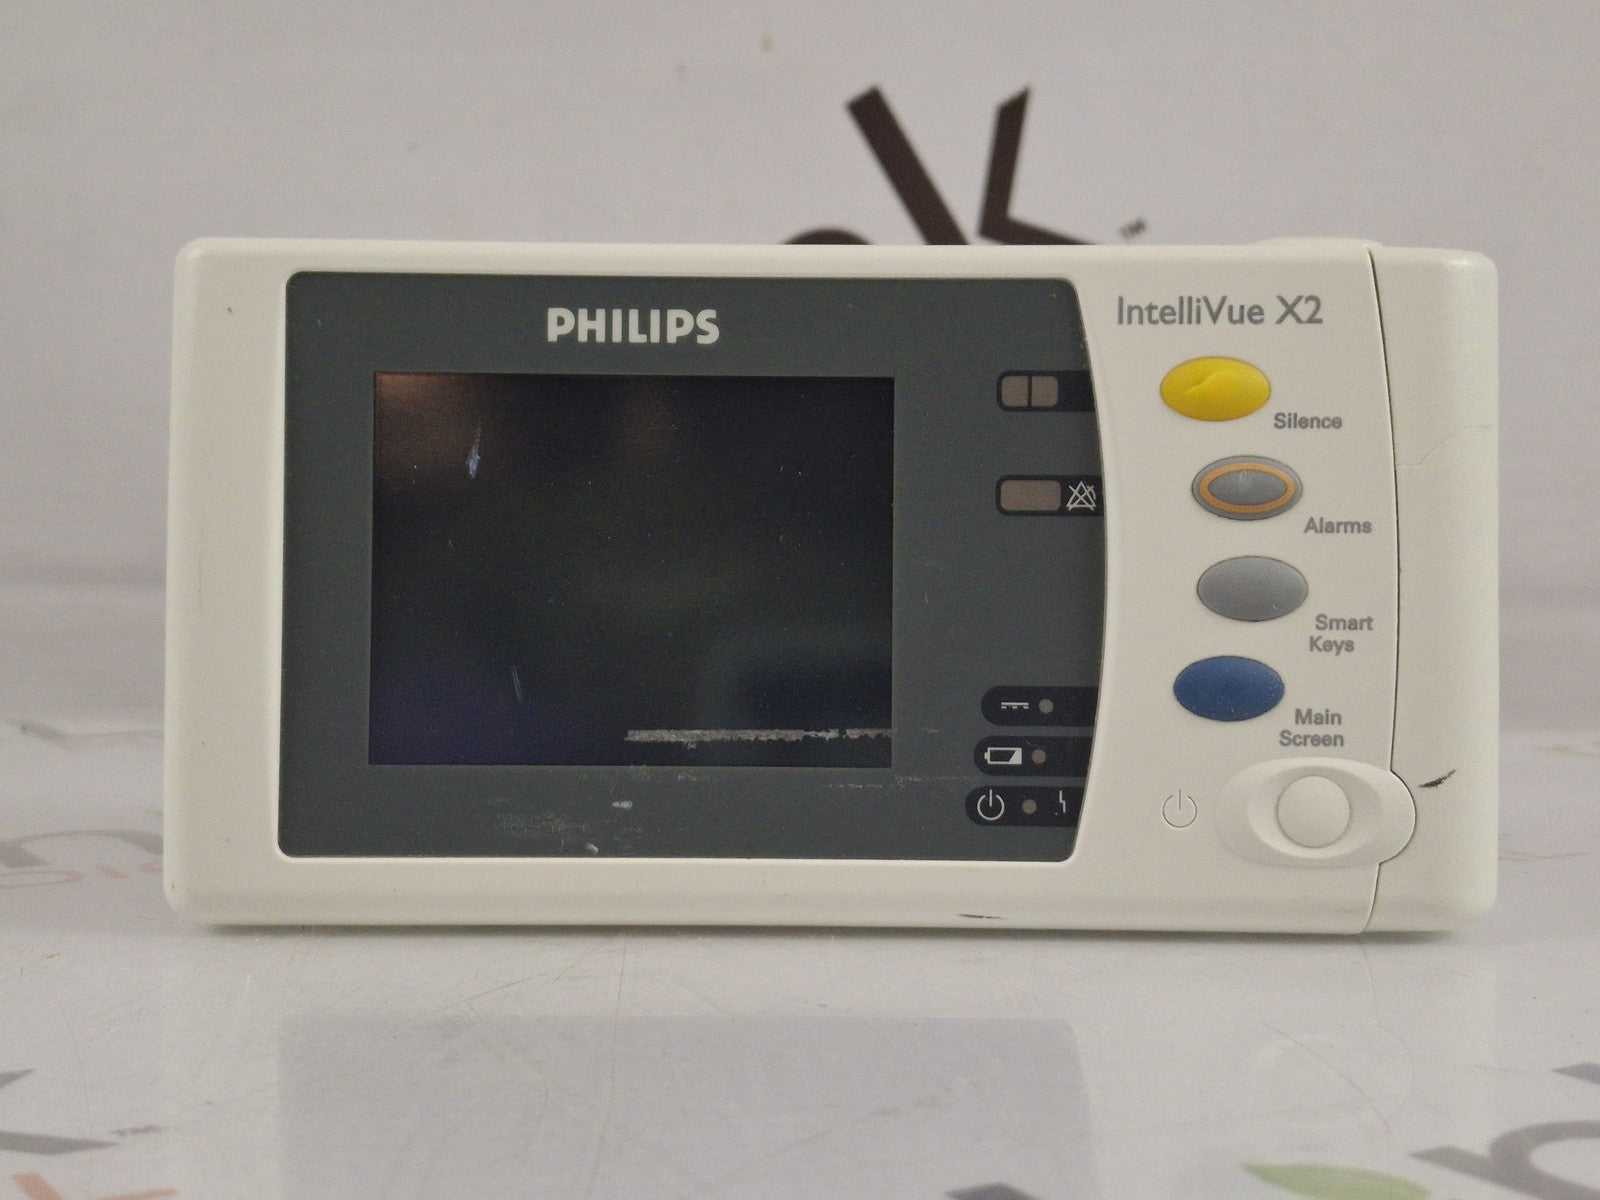

PHILIPS INTELLIVUE MX450 BEDSIDE PATIENT MONITOR

Sale price$ 1,500.00

PHILIPS INTELLIVUE MX450 BEDSIDE PATIENT MONITOR

Sale price$ 1,500.00